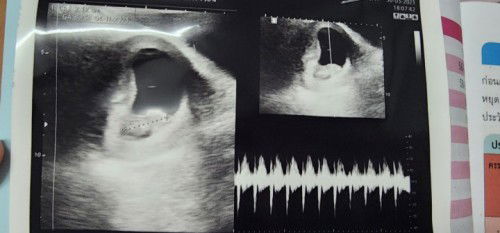

ซาวด์รอบแรกหมอบอกท้องได้ 8 สัปดาห์ 5 วัน

ซาวด์วันที่ 30/03/23 หมอบอกน้องได้ 8 สัปดาห์ 5 วัน พอซาวด์ล่าสุดวันที่ 11/04/23 หมอบอกน้องได้ 11 สัปดาห์ 2 วัน ถ้านับตามครั้งแรก น้องจะได้ 10 สัปดาห์ 3 วัน สรุปจริงๆแล้วน้องได้ 11 สัปดาห์แล้วใช่มั้ยคะ สับสนนิดหน่อย